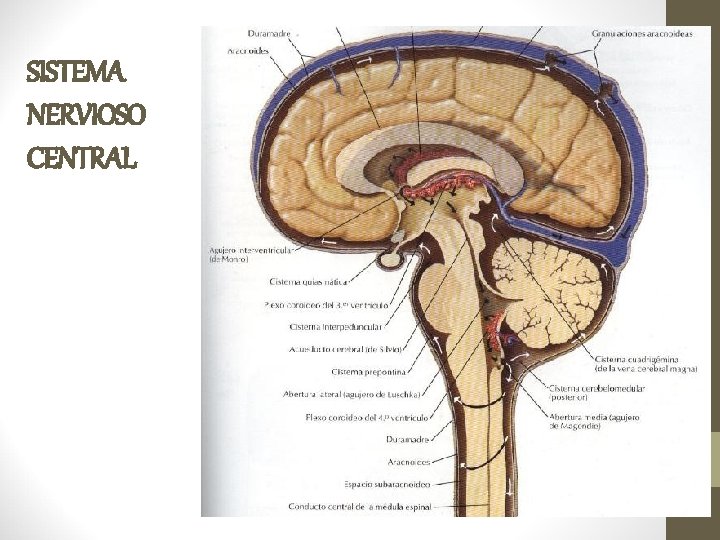

SISTEMA NERVIOSO CENTRAL